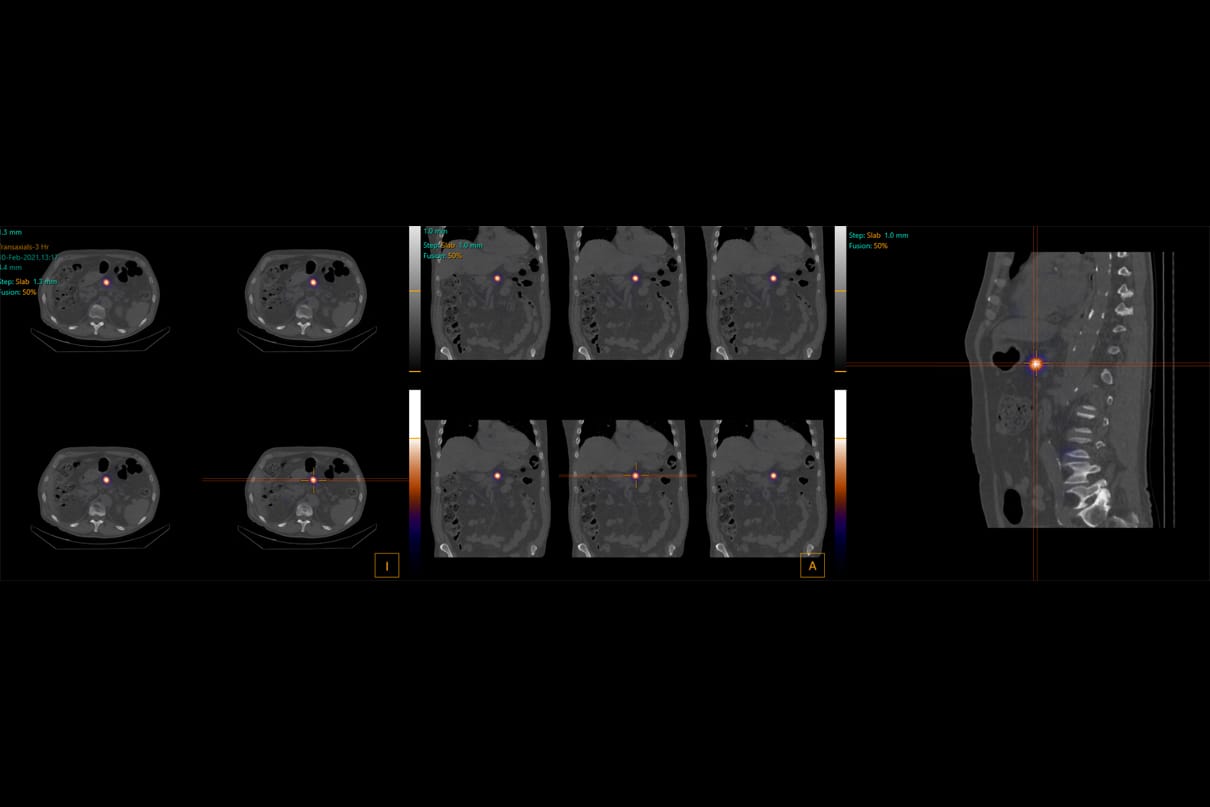

The Clatterbridge Cancer Centre in Liverpool has partnered with Canadian software company Limbus AI to trial and co-develop a commercial AI-based autocontouring tool for brachytherapy cervical cancer treatment. Brachytherapy involves placing an intense radiation source inside or in close contact with tumour cells. This makes it well suited to treating tumours in particular parts of the body such […]